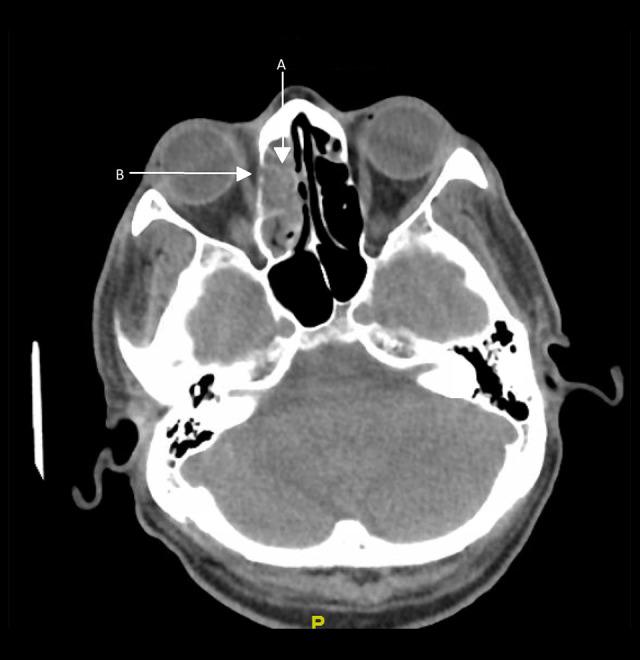

BACKGROUND We present a case of invasive sinusitis with rhinocerebral infection in a patient who had mild symptoms of COVID-19 infection and did not receive any immunosuppressive therapies. CASE REPORT A 49-year-old man with a history of uncontrolled diabetes presented to the hospital with multiple generalized tonic clonic seizures. He had recently been diagnosed with mild COVID-19 and was treated at home with supportive care only. He was found to have cerebritis in the right frontal lobe along with right fronto-ethmoid sinusitis. He underwent extensive testing with nasal endoscopy with gram stain and culture, cryptococcal studies, 1-3-Beta-D glucan, blood cultures, fungal CSF studies, Lyme disease, HIV, Fungitell assay, and galactomannan studies, which were all negative. He was started on i.v. antibacterial therapy with cefepime, vancomycin, and metronidazole along with amphotericin B. After 2 weeks, his repeat imaging revealed progression of cerebritis along with new early abscess. Given these findings, his antibiotics were changed to meropenem and the amphotericin B dose was increased. He was recommended debridement and sinus surgery but refused. During the course of treatment, he developed acute kidney injury and was switched to Posaconazole. Unfortunately, the patient decided to leave against medical advice 6 weeks into admission. He was advised to continue Posaconazole and levofloxacin but he could only afford levofloxacin. He was then recommended long-term levofloxacin. He has since recovered, with resolution of cerebritis noted in follow-up imaging 1 year later. CONCLUSIONS Our patient had mild COVID-19 infection and presented with secondary infective complications, which are usually associated with an immunocompromised state, despite receiving no immunosuppressives. It is imperative that all clinicians treating COVID-19 be watchful for fungal or bacterial co-infections in patients with active SARS-CoV-2 infection, even if the presenting symptoms are mild, particularly if other risk factors are present.

一名 49 岁男性,有未控制的糖尿病病史,因多发性全面强直阵挛发作到医院就诊。他最近被诊断为轻度 COVID-19,仅在家接受支持治疗。他被发现右额叶脑炎症伴有右额窦-筛窦炎。他接受了广泛的检查,包括鼻内镜革兰氏染色和培养、隐球菌研究、1-3-β-D 葡聚糖、血培养、真菌性 CSF 研究、莱姆病、HIV、Fungitell 检测和半乳甘露聚糖研究,结果均为阴性。他开始接受头孢吡肟、万古霉素和甲硝唑联合两性霉素 B 的静脉抗菌治疗。2 周后,他的重复影像学检查显示脑炎症进展,并出现新的早期脓肿。鉴于这些发现,他的抗生素改为美罗培南,并增加两性霉素 B 的剂量。他被建议行清创术和鼻窦手术,但被拒绝。在治疗过程中,他发生急性肾损伤,改为伏立康唑。不幸的是,患者在入院 6 周后决定出院。他被建议继续服用伏立康唑和左氧氟沙星,但他只能负担得起左氧氟沙星。然后建议他长期服用左氧氟沙星。1 年后的随访影像学检查显示脑炎症已消退,他已康复。